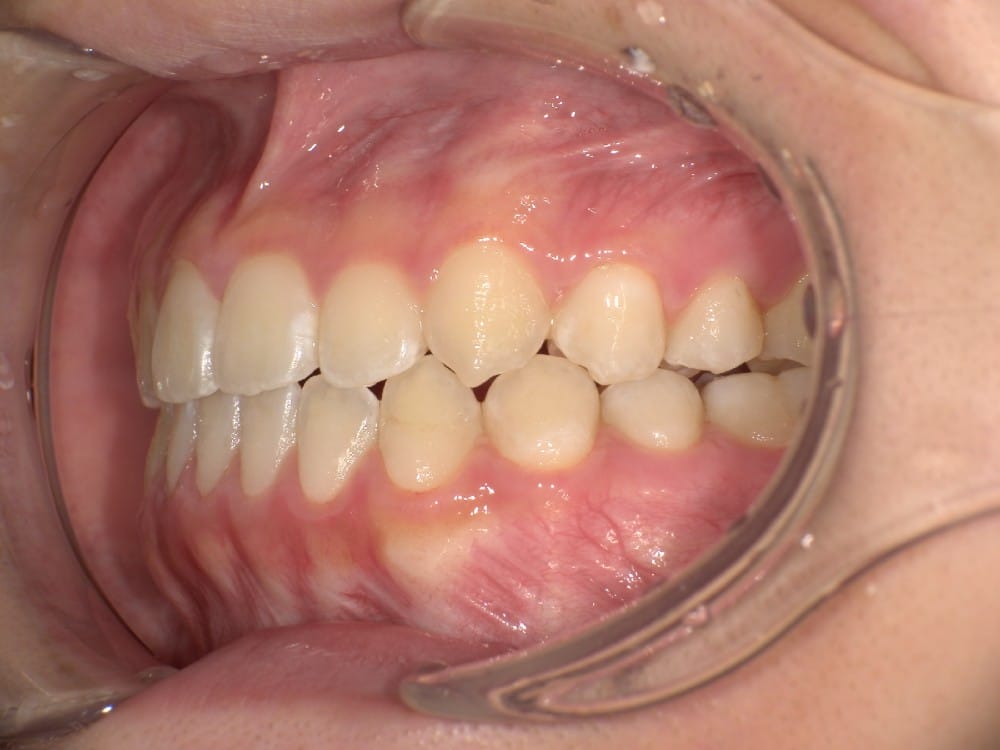

30代の男性で、受け口とガタガタを主訴にご来院されました。

治療前の様子

分析しますと

- 骨格的な上下あごの前後差は重度

- 噛み合わせの位置も下あごの奥歯が半分くらい前にズレていた

- 上の前歯が前に傾斜、下の前歯が内側に傾斜しているにもかかわらず、受け口

というケースで、外科的な処置も検討するようなケースでした。

骨格的なズレや奥歯の噛み合わせのズレもあり、重度の受け口でしたが、なんとか歯列矯正のみで受け口を改善できると診断し、治療を開始しました。

先ほどの2ケースと同じように、患者さまに外科的な手術の選択肢も提示しましたが、希望されず、横顔の変化はおそらく起こらないことを納得の上、治療をスタートいたしました。

今回のケースも奥歯の移動量が大きいため、マウスピースだけでは難しいと判断し、カリエールとよばれる装置を補助的に使用し、上下の噛み合わせの前後関係を整えることで、手術を行わずに機能面と見た目の両方が改善することにしました。

治療後の写真です。

<治療前後の比較です>

正面から見た時の受け口は改善していますが、横顔の変化は軽微かほとんど起こっていません。

同じように治したケースでも横顔の変化には差があります。

だからこそ、治療前に「どこまでを目標にするのか」をしっかり共有し、噛み合わせ改善を軸に治療を進めることが大切になります。